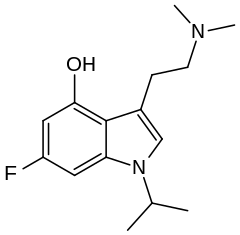

| O-4310 | artificial | 1-CH(CH3)2, 4-OH, 6-F | CH3 | CH3 | 3-[2-(dimethylamino)ethyl]-6-fluoro-1-isopropyl-1H-indol-4-ol | 885671-63-6 |